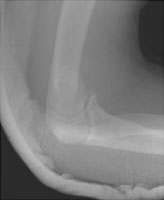

Supracondylar Fracture (Humerus)

Fractures of the distal humerus usually involve the supracondylar portion of the humerus and are extraarticular. Less common fractures of this region include transcondylar, bicondylar, and intercondylar fractures which involve the articular surface of the elbow (and are termed intraarticular). Volkmann's ischemic contracture (due to decreased blood supply) of the hand is a known complication of the supracondylar fracture. The supracondylar fracture is generally due to hyperextension injury due to a fall on an outstretched hand.

- Click on the image for a larger versionALateral radiograph of the elbow.